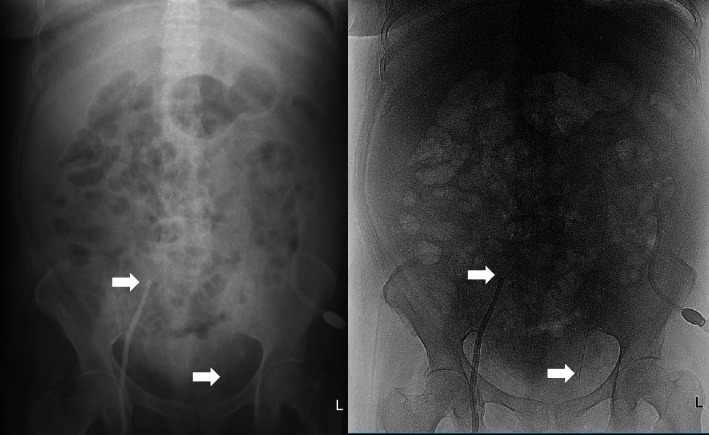

A 67-year-old woman was diagnosed with chronic kidney disease stage V, severe uremia syndrome, hyperkalemia, metabolic acidosis, suspected pulmonary oedema, and multiple hemodialysis access failure. The patient is in a condition that requires emergency hemodialysis, but the patient does not have any access to undergo hemodialysis. The patient then underwent acute peritoneal dialysis and received an adequate response. The patient continued continuous ambulatory peritoneal dialysis and responded well.